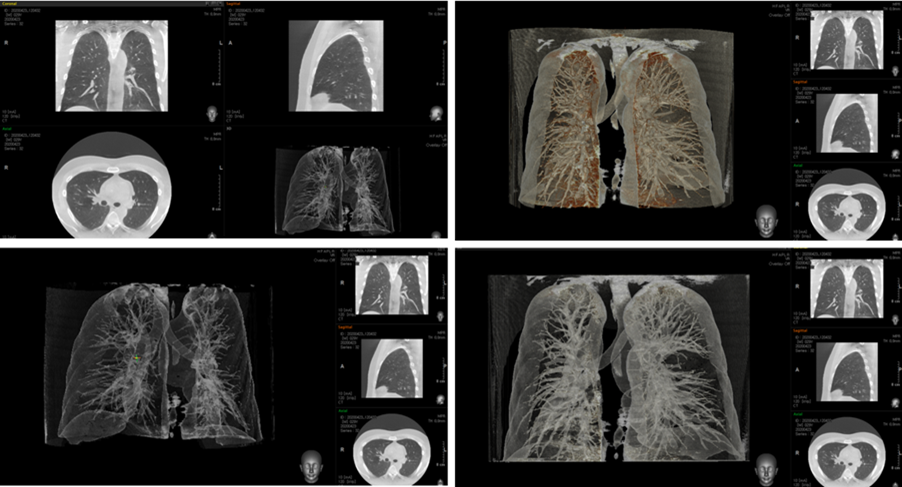

바텍이 개발한 소형 CT ‘스마트 엠(Smart M)’은 폐렴 진단 기능을 보유, 코로나 19 등 바이러스성 폐렴 진단이 가능하다. 인공지능(AI) 진단 기능도 지원한다.

스마트 엠은 법규상 CT 도입이 어려운 200병상 미만 중소병원, 요양병원, 정형외과 등에 설치 가능하다. 두부, 경추, 팔, 다리, 관절 부위를 고해상도로 촬영할 수 있어 교통사고 환자의 두부ㆍ경추, 노인성 폐렴, 사지 관절 진단ㆍ치료에 획기적으로 기여할 수 있을 것으로 기대된다.

전신CT(MDCT) 대비 1/5 수준 가격으로 중소병원의 CT 도입에 따른 투자 비용부담을 획기적으로 낮췄다. 3m X 2m 면적이면 설치할 수 있을 정도로 사이즈가 컴팩트하며 전신 CT와 달리 가정용 전원을 사용할 수 있어 추가 시설공사 부담 없이 도입 가능하다. 직접 개발한 고성능 디텍터를 장착해 피폭 선량은 전신 CT 대비 1/10 수준으로 낮추면서 고해상도를 구현했다.